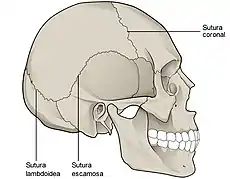

Cráneo de un recién nacido. Son visibles las suturas entre los huesos del cráneo que corresponden a una articulación de tipo sinartrosis con nula movilidad. | ||

Las funciones más importantes de las articulaciones son constituir puntos de unión entre los componentes del sistema óseo (hueso, cartílagos), y facilitar movimientos mecánicos, proporcionándole elasticidad y plasticidad al cuerpo. Algunas articulaciones no son móviles, como las que se establecen entre los huesos del cráneo, sin embargo son de gran importancia pues permiten la protección del encéfalo y hacen posible al mismo tiempo su crecimiento durante la infancia.

Fibrosas

Son aquellas en que los extremos de los huesos están unidos por tejido fibroso. Este tipo de articulaciones tienen muy poca movilidad. Un ejemplo de articulación fibrosa son las suturas que unen los huesos del cráneo. Un tipo particular de articulación fibrosa es la sindesmosis en la que dos huesos se unen mediante una lámina de tejido fibroso, como ocurre en la membrana interósea del antebrazo que une el cúbito con el radio. Un caso particular es la sindesmosis dentoalveolar, también llamada gonfosis, que es una articulación fibrosa, sin movimiento en condiciones normales, que se establece entre la raíz de una pieza dental y la apófisis alveolar situada en la mandíbula.[7]

Sinartrosis

Las sinartrosis son articulaciones que tienen muy poca movilidad. Las uniones entre los huesos que forman el cráneo se llaman suturas y son un buen ejemplo de sinartrosis.[9] Dependiendo del tipo de tejido que sirve de unión, se dividen en:

- Sinfibrosis, cuando el tejido de unión es fibroso como en las suturas entre los huesos del cráneo.